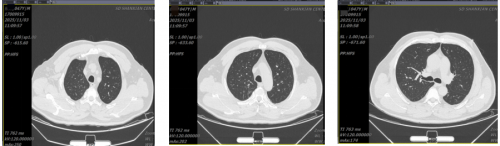

10月27日胸部CT示:双肺间质性改变;双侧胸腔积液并双肺下肺膨胀不全。